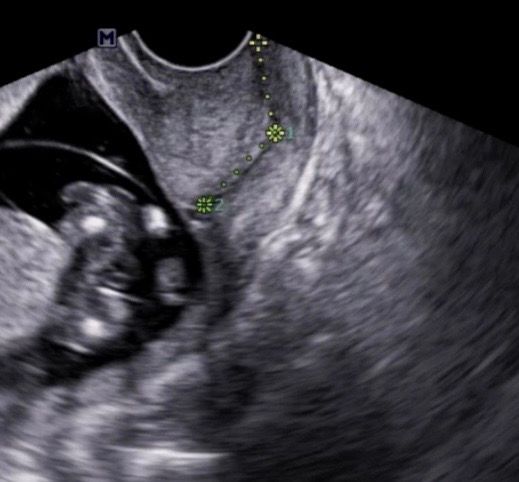

자궁경부길이 관련 사진입니다. 많은 답변 부탁드려요.

각자 다른 원장님께서 측정해주신 자궁경부 길이입니다.

첫번째사진은 끝쪽까지 길이를 재주셨는데

두번째사진은 중간까지 길이만 재주셔서요..!

왜 다를까요?????